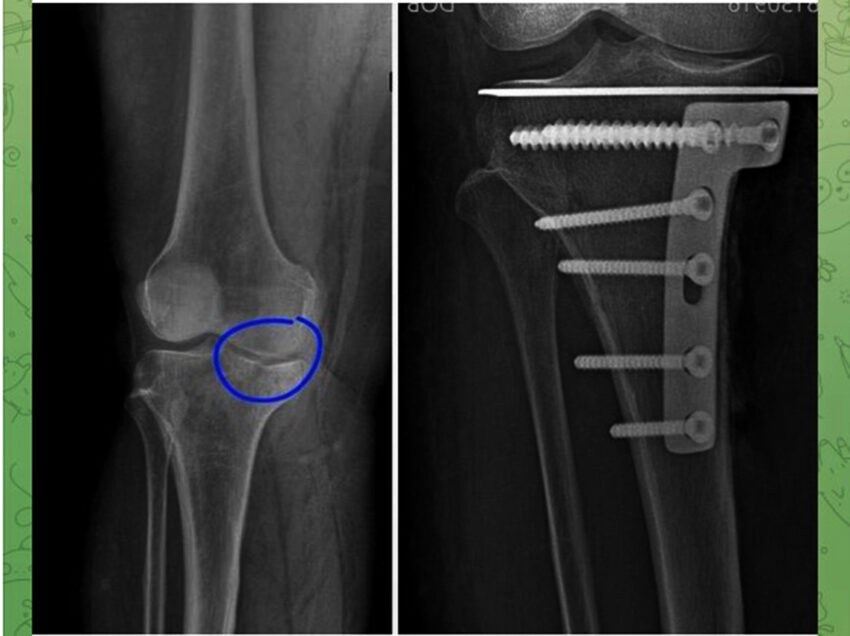

В Воронеже медики впервые провели операцию на колене, не вскрывая сустав. 56-летняя пациентка обратилась к врачам с жлобами на боль в колене, которая возникла после падения с лестницы. В травматологическом отделении ВГКБ №2 обследовали женщину, и выяснилось, что у нее оскольчатый компрессионный перелом медиального мыщелка левой большой берцовой кости со смещением отломков и кровоизлияние в полость левого коленного сустава. Бригада травматологов-ортопедов решила обратиться к остеосинтезу внутрисуставные компрессионных переломов под контролем артроскопии (с ее помощью врачи определили зону повреждения) — способу, который ранее не использовался в их практике. Без вскрытия сустава медики сопоставили отломки, после чего зафиксировали их спицей, опорной титановой платиной и винтами. В больнице отметили, что операция прошла успешно и у женщины, которая пока еще находится в стационаре, прогнозы благоприятные. Поскольку операция была малоинвазивной и малотравматичной, срок реабилитации будет н

В Воронеже медики впервые провели операцию на колене, не вскрывая сустав. 56-летняя пациентка обратилась к врачам с жлобами на боль в колене, которая возникла после падения с лестницы. В травматологическом отделении ВГКБ №2 обследовали женщину, и выяснилось, что у нее оскольчатый компрессионный перелом медиального мыщелка левой большой берцовой кости со смещением отломков и кровоизлияние в полость левого коленного сустава.

Бригада травматологов-ортопедов решила обратиться к остеосинтезу внутрисуставные компрессионных переломов под контролем артроскопии (с ее помощью врачи определили зону повреждения) — способу, который ранее не использовался в их практике. Без вскрытия сустава медики сопоставили отломки, после чего зафиксировали их спицей, опорной титановой платиной и винтами.

В больнице отметили, что операция прошла успешно и у женщины, которая пока еще находится в стационаре, прогнозы благоприятные. Поскольку операция была малоинвазивной и малотравматичной, срок реабилитации будет не долгим, да и риск послеоперационных осложнений сводится к минимуму.